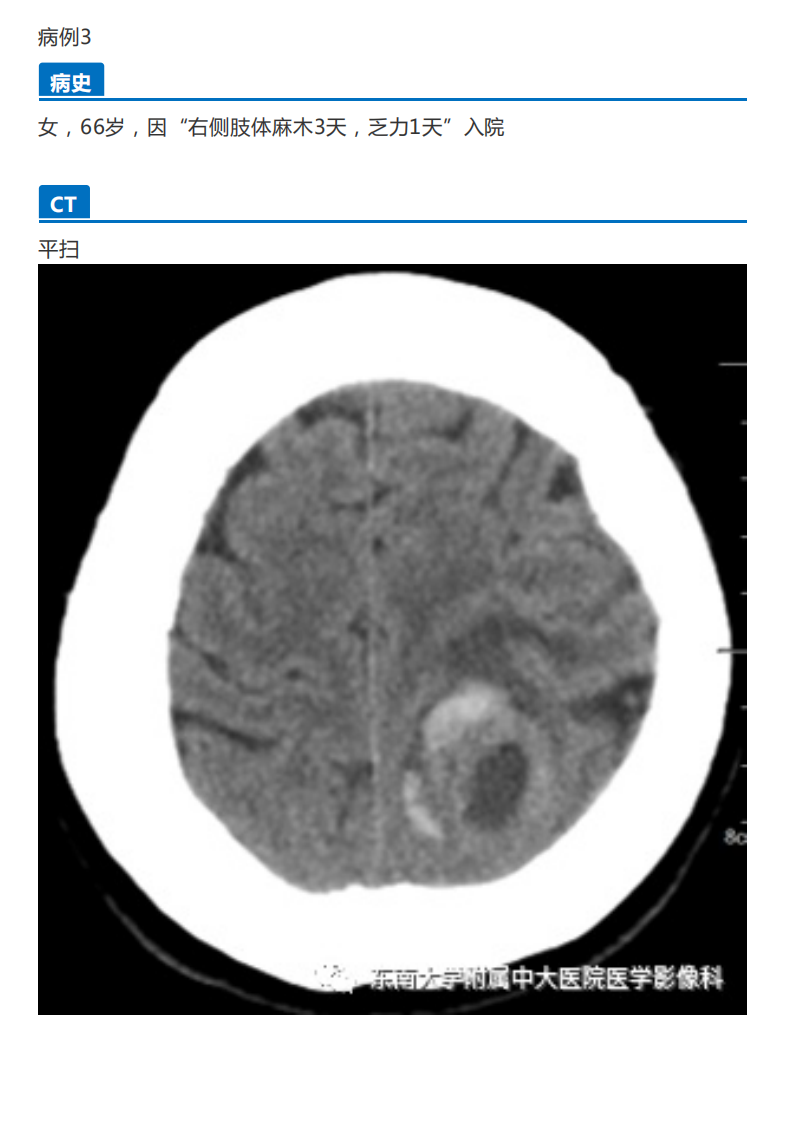

20190909_2【晨读结果公布】2019.09.09神经系统疾病.pdf